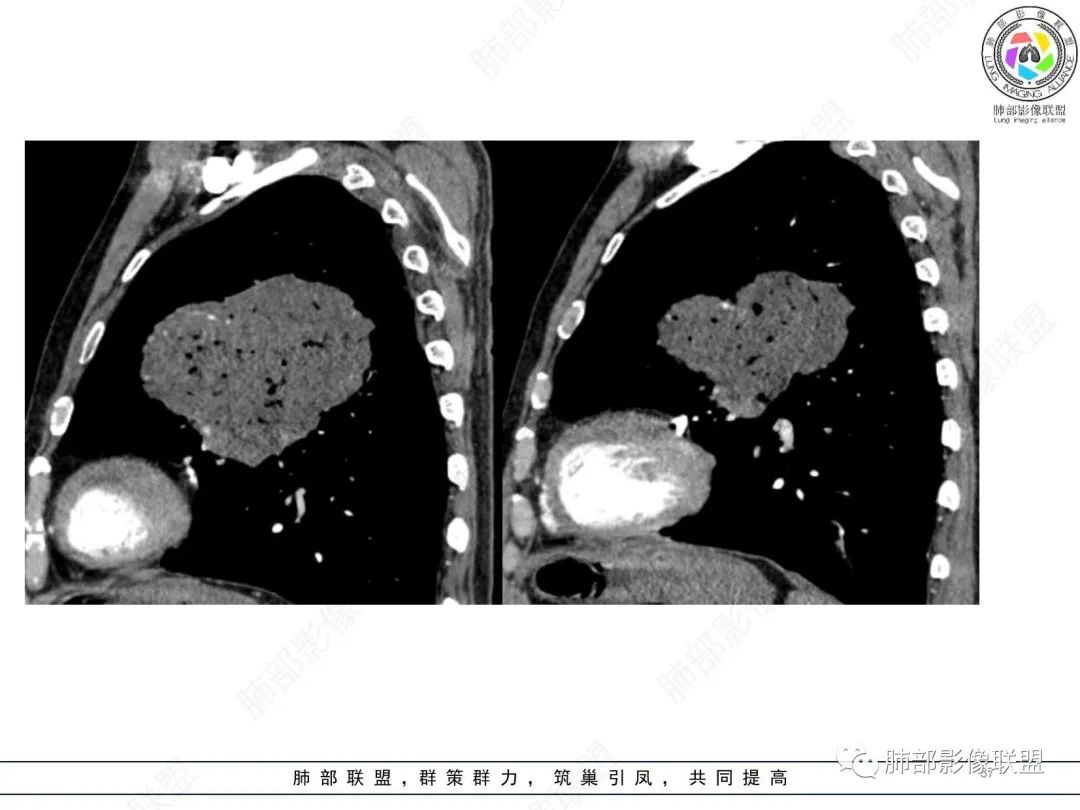

左肺上叶大肿块,膨胀性生长,边界清,密度较低,见部分坏死区,强化弱,肿块见支气管充气V扩张征,分布僵直,枯树枝特点,另一个重要特点血管造影征,淋巴瘤,肿块长轴与胸膜平行,与隐球菌鉴别,隐球荚膜抗原检查,明确诊断经皮肺穿刺。另胸膜钙化(问诊既往有无患胸膜炎病史)。

左肺上叶胸膜下肿块,宽基底与胸膜相连,跨叶裂,边缘清晰膨隆,其内支气管充气,部分扩张、僵直,无明显强化,血管造影征,考虑淋巴瘤,鉴别腺癌

左肺胸膜下巨大占位,跨叶裂,宽基底与胸膜相连,胸膜钙化,平扫密度较低,强化不明显,可见内部血管显影,支气管充气征和扩张,考虑为恶性,倾向于淋巴瘤

支持淋巴瘤,左上肺大肿块,有分叶,边缘光整,病灶内密度不均,可见支气管扩张征,增强后可见血管影征。周围肺野清晰。

左肺上叶肿块,宽基底与胸膜相连,跨叶裂,边缘清晰膨隆,可见小分叶,其内支气管充气,部分扩张、僵直,呈枯枝征,支气管达边征,增强无明显强化,可见血管造影征,考虑恶性病变,淋巴瘤,鉴别粘液腺癌。

大肿块,边缘光滑,深分叶

近端支气管堵塞、推移为主

部分类似于脐凹征

内部支气管扩张

肺动脉推移为主,边缘部分进入

1)部位:周围型或中央型软组织肿块,以周围型为多见,且肿瘤多位于肺上叶。如本例:该肿瘤位于左肺上叶。

2)大小及形态:由于本病恶性程度高,早期症状不明显,发现时肿块均较大。如本例病变巨大。

3)肿块边界和边缘:多较清楚,呈圆形、类圆形,且由于肿块生长速度不均匀,可见分叶,毛刺少见。有报道肿块周围毛玻璃影是多形性癌特征表现。

4)密度:肿块平扫为软组织密度,由于体积较大,内部常见大片状坏死,可出现不规则厚壁空洞或坏死内多发无壁小空洞,坏死多不均匀:坏死灶内可见如柳絮样的斑片样强化灶,坏死边缘与非坏死区分界不清本例坏死较明显,密度不均匀。

5)肿瘤强化方式:肺部恶性肿瘤强化程度与其血供丰富程度相关,血供丰富多强化明显,反之则较差。由于PSC 周边实性部分富血供及内部黏液变性、坏死,增强后肿块多数呈轻-中度边缘环形强化或不均匀小斑片状强化。国外学者对照病理发现肿瘤细胞或胶原组织增强扫描时强化,无强化的低密度区代表了黏液样变性区和出血坏死区。